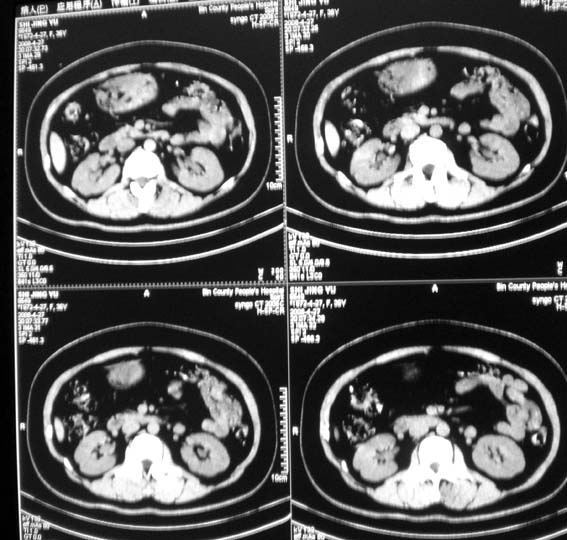

标题: CT13126:腰痛,肾区痛。

女,36岁,腰痛,肾区痛曾有肾囊肿史。

腹部未见明显异常

髓质海绵肾?建议mr。